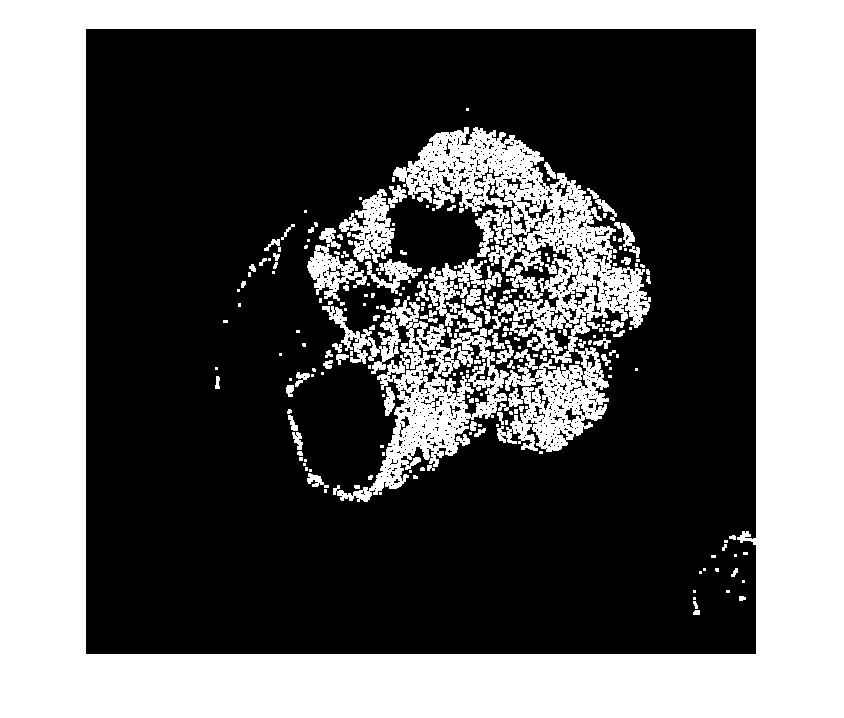

%---------------------------------------------------- % Normalize input data to range in [0,1]. Xmin = min(imLowResL(:)); Xmax = max(imLowResL(:)); if isequal(Xmax,Xmin) imLowResL = 0*imLowResL; else imLowResL = (imLowResL - Xmin) ./ (Xmax - Xmin); end % Threshold image - global threshold BW = imbinarize(imLowResL); % Invert mask BW = imcomplement(BW); % Open mask with square width = 3; se = strel('square', width); BW = imopen(BW, se); %---------------------------------------------------- imshow(BW)

Создайте bigimage от маски с той же пространственной ссылкой как маска ввода.

Отобразите маску с зеленым фоном.

h = bigimageshow(bim); h.Parent.Color = 'g'; h.Parent.Alphamap = [1 .5]; h.AlphaData = bmask; h.AlphaDataMapping = 'direct';